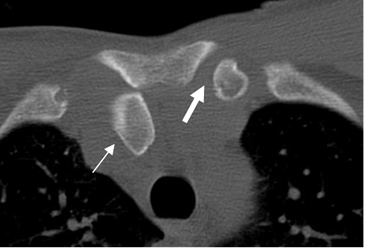

Fig 30 A. Luxación esternoclavicular.

TAC axial. Luxación con desplazamiento posterior, del tercio proximal de la clavícula derecha. (Flecha delgada). Lado izquierdo articulación en posición normal. (Flecha gruesa).